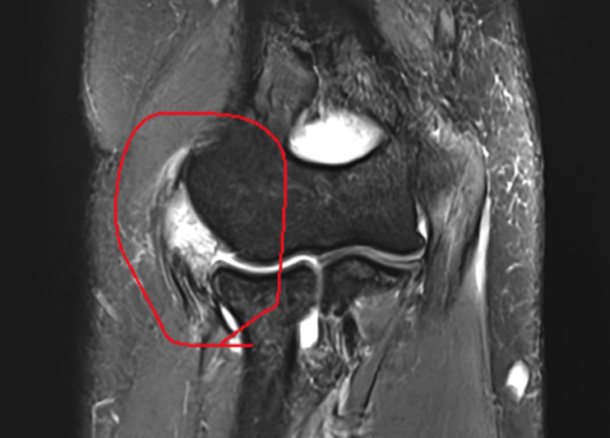

After 수술 후

1년 후 완전 정상화